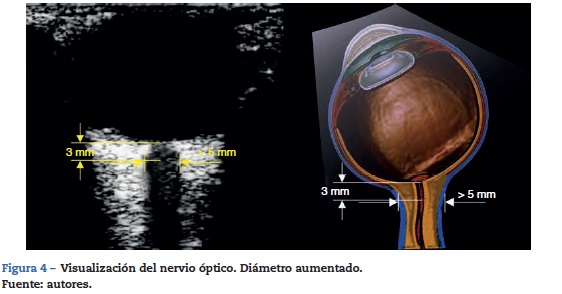

Se debe contar con un transductor lineal de alta frecuencia (7-10 mhz)22. El ecógrafo se configura para permitir visualizar estructuras hasta 5-6 cm de profundidad. El transductor se ubica sobre el párpado del ojo cerrado previa aplicación de abundante gel conductor.

El nervio óptico se identifica como la estructura hipoecoica de trayecto regular posterior al globo ocular. El estándar de medición requiere trazar una línea vertical que se inicia en la unión del nervio óptico con el globo ocular; esta línea es simplemente una referencia y debe medir 3 mm. Una vez localizados estos 3 mm se traza una línea horizontal de borde a borde del nervio óptico; esta segunda línea es la que mide el valor en milímetros del nervio óptico (figs. 3 y 4)32,33.

Para la mayoría de los autores revisados 5 mm es el punto de corte para que el estudio se considere positivo para hipertensión endocraneana; otros autores proponen valores diferentes (tabla 1).

Se resalta una revisión sistemática publicada en 2011 de Dubourg et al.33 y que evaluaba la precisión diagnóstica de la medición del nervio óptico en comparación con la medición invasiva de la presión intraparenquimatosa como el estándar de oro; se incluyeron 6 estudios prospectivos de cohorte con un total de 231 pacientes sin detectarse heterogeneidad significativa para la sensibilidad y la especificidad de la medición ultrasonográfica33. La medición de la vaina del nervio óptico tiene una sensibilidad de 0,90 (IC 95%: 0,80-0,95) una especificidad de 0,85 (IC 95%: 0,73-0,93). Esta revisión también mostró una fiabilidad entre los evaluadores de 0,2 a 0,3 mm. Su inconveniente es que no se contó con un valor de corte preciso para definir la dilatación de la vaina del nervio óptico en todos los estudios. La medición del diámetro de la vaina del nervio óptico demuestra buena precisión diagnóstica para detectar la hipertensión intracraneal e influye en la decisión de remitir a los pacientes a centros especializados33.